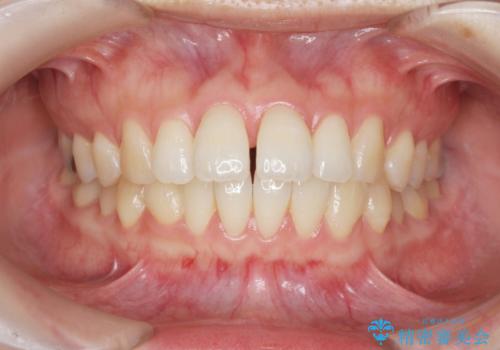

- 出っ歯に見える前歯を治したい、と矯正治療を希望され来院されました。

奥歯の噛み合わせに大きな問題はないので、目立つ前歯の角度・隙間を重点的に整え、審美的な歯並びを獲得できるよう計画します。

治療によりしっかりと前歯の角度が改善され、審美的な歯並びを手に入れることができました。